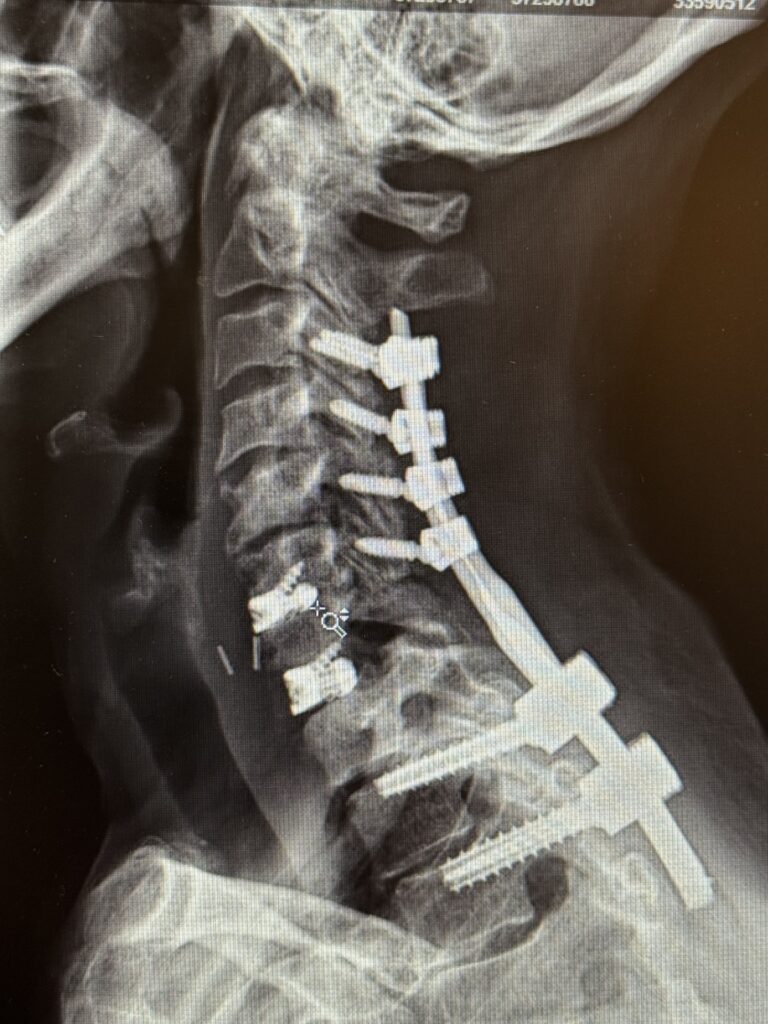

Back:

Revision Surgery Treats Intractable Neck Pain & Cervical Deformity

Author: Benjamin R. Cohen M.D., F.A.A.N.S., F.A.C.S., Read More!